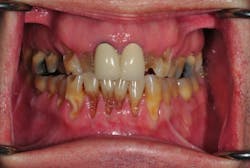

Before we start prepping teeth, we have to be certain that our foundation is sound, which means establishing biologic health, including addressing periodontal concerns and caries control.

Dentists often have to sequence more complex treatments because of time, finances, and other factors. How can we sequence treatment in a way that allows the patient to function between phases? How can we approach this complex system as a series of simple steps?

4. Idealize the lower arch first, when possible. The lower incisal edges determine the position and lingual contour of the upper anterior teeth, so this is the best place to start. These initial restorations can be done with provisionals, composite resin, or porcelain, depending on the scope of work to be done, financial considerations, and the phasing of your plan.